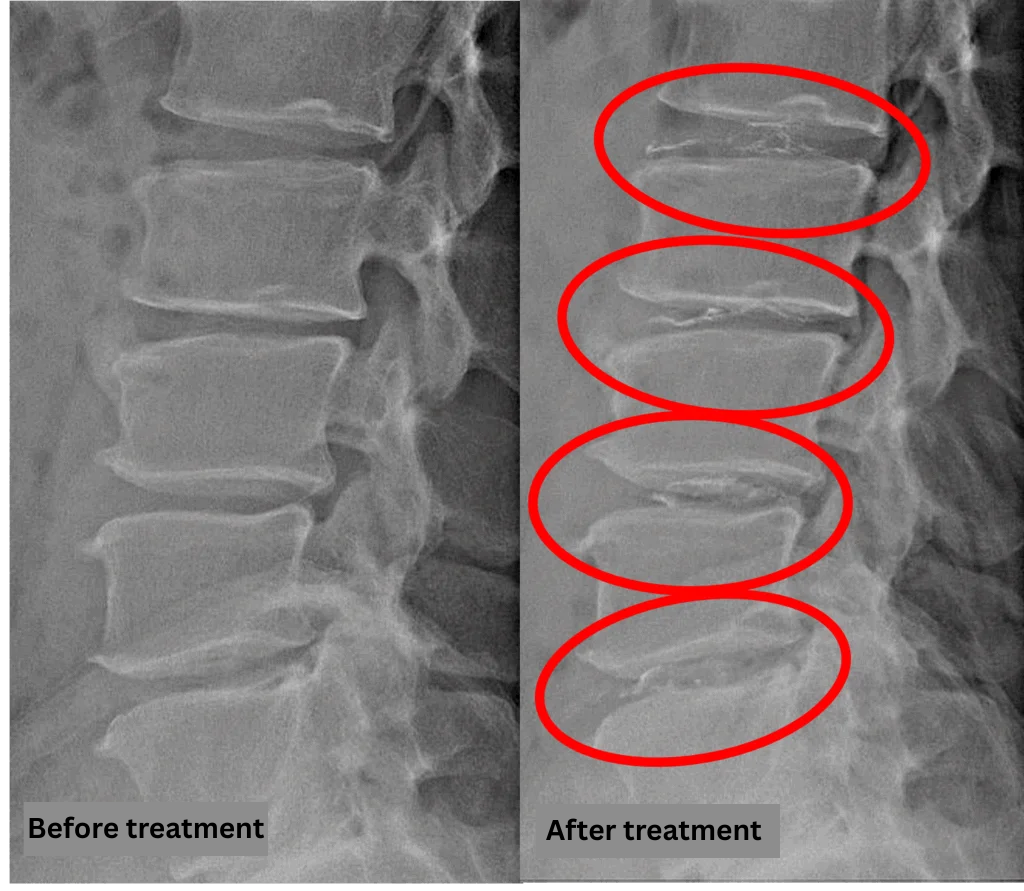

- L2/3, L3/4, L4/5, L5/S: disc degeneration and protrusion

The above findings were also observed on the imaging.

Compression of the spinal canal caused by degenerative changes at L2/3, L3/4, L4/5, and L5/S is the most likely source of symptoms.

After consulting with the patient, the Cellgel Method was performed on L2/3, 3/4, 4/5 and 5/s.